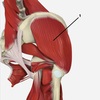

1

gluteus medius

57

gluteus maximus

58

gluteus minimus

59

tensor fascia lata (thickens lateral to form iliotibial tract)

60

tensor fascia latae

61

2

gluteus medialis

62

3

63

4

iliotibial tract (2 muscles attach) 1. tensor fascia lata 2. gluteus maximus provides stabalisation to lateral aspect of the knee